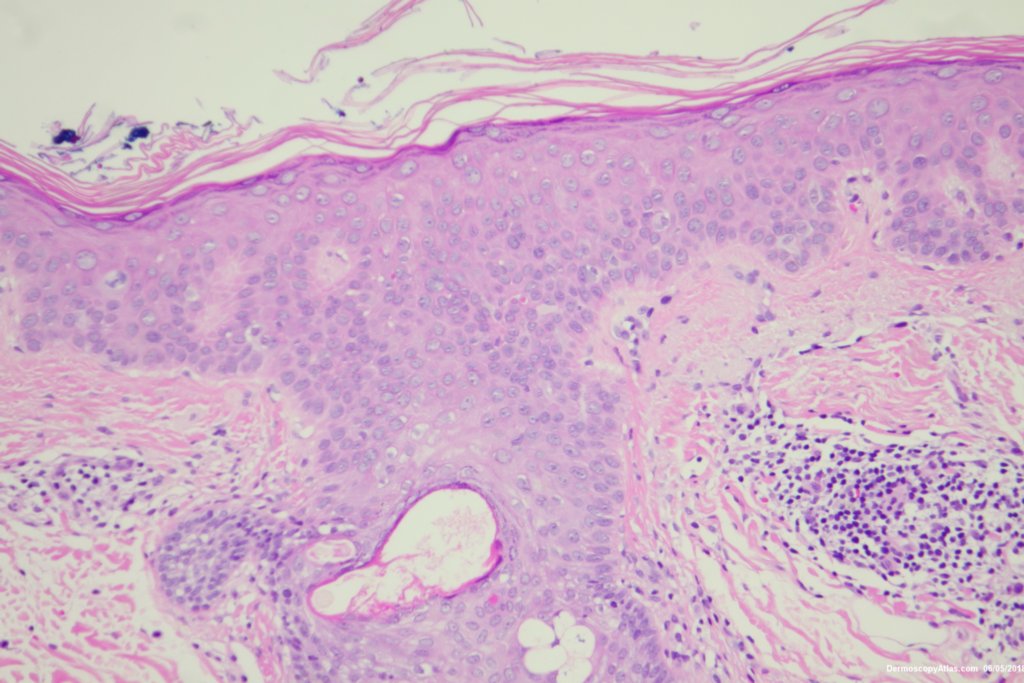

Diagnosis: Pigmented Intraepidermal carcinoma

Some pigmented lesions look melanocytic, However this is a pigmented intraepidermal carcinoma. Some areas show more full thickness atypia than others. The dermatoscopy shows some dots in rows but there are other grey dots showing regression at one edge.